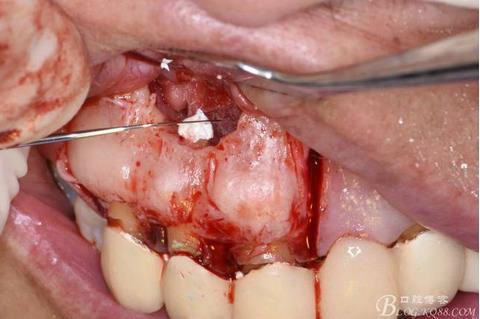

圖9.去除唇側(cè)薄的骨壁,暴露出囊壁

圖10.剝離囊壁